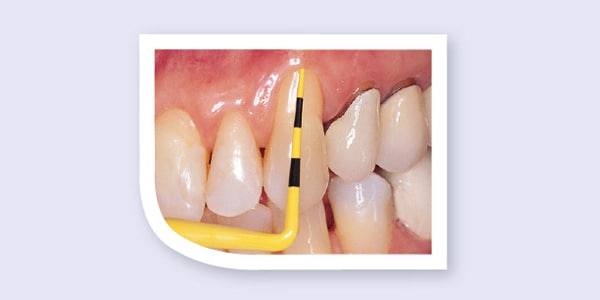

Compare the Colorvue probe to a standard metal probe. Colorvue's yellow tip with black markings provides superior contrast to the gingival tissue when measuring pocket depth.